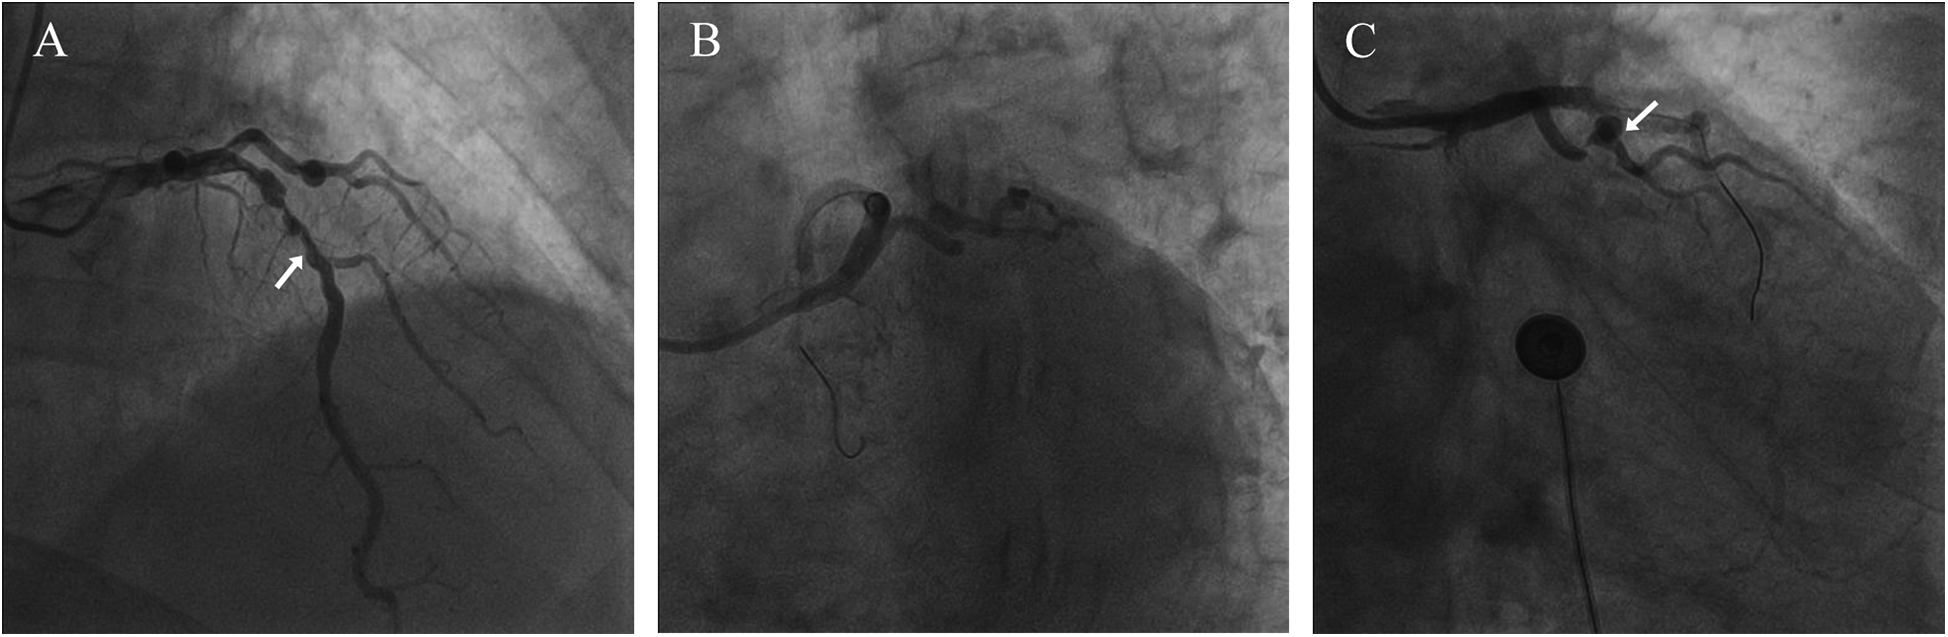

Figure 1

Coronary angiography results. (A) The arrow points to the LAD (B) severely stenosed and tortuous coronary artery (C) the arrow points to the loop-like vascular structure.